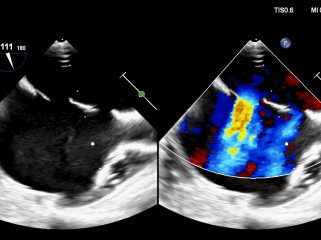

双封堵器释放后超声

CDFI:AR(-),MR(少量),TR(少量)。房间隔中部探及两处封堵器回声,房水平未见明显分流。室间隔连续完整,室水平未见明显分流。肺动脉内径不增宽。升主动脉内径23mm。心包腔内未见明显液性暗区。

《常见先天性心脏病介入治疗中国专家共识》指出:对于存在2个ASD,但缺损间距≤7mm,可选择1枚封堵器闭合;多个缺损的间距>7mm,无法采用1枚封堵器实施介入治疗,需要选择2~3枚封堵器分别闭合[1]。本例食道超声示两处缺损(回声中断8.06mm,分流束宽5.63mm),两个缺损之间相距8.48mm,术中通过超声精准指导,先植入BDASD-I16封堵器封堵8.06mm缺损,再测量第二个缺损约5mm后,植入BDASD-I10封堵器,术后即刻超声显示,两枚MemoSorb可降解封堵器位置形态理想,无残余分流,封堵成功。